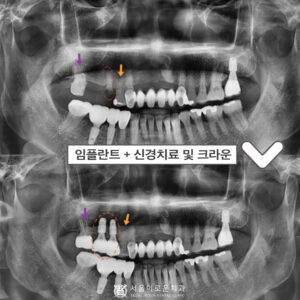

부천서울이로운치과 과거에 치료받았던 보철이 불편하다면? 안녕하세요! 부천서울이로운치과 대표원장 이경중입니다 🙂 앞니는 어금니와 달리 우리가 말할 때나 음식을 먹거나 미소를 지을 때 외부로 드러나 보이는 부분이기 때문에 심미적인 부분에서도 중요한 부분을 차지하게 되는데요. 그렇게 때문에 적절하지 못한 보철물로 인해 보기 좋지 않거나, 잇몸 건강에 문제가 있는 경우 재보철을 통해 더보기…